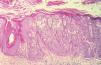

Se ha descrito una amplia variabilidad de hallazgos histopatológicos en la EV6. En ocasiones los hallazgos son similares a los de las verrugas planas, aunque afectando casi la totalidad de la epidermis y con una mayor vacuolización citoplasmática. También es frecuente encontrar efectos citopáticos provocados por el VPH (granos de queratohialina más grandes y numerosos, coilocitosis, papilomatosis, etc.)7. Un efecto citopático característico de los VPH-EV es el hallazgo de células «hinchadas» (células EV), claras, grandes, ovaladas o redondeadas, con una apariencia globulosa y con vacuolización o microgránulos en su citoplasma. Suelen localizarse en el estrato granuloso de la epidermis y en ocasiones se agrupan formando nidos6. En la EV se pueden observar también células displásicas, o cambios celulares malignos, hacia EB y CE principalmente (con unos hallazgos histológicos similares a los de la EB o el CE, aunque con un mayor grado de disqueratosis)6.

Células EV. Existencia de células similares a las observadas en la EV: grandes, de citoplasma microgranulado y grisáceo, redondeadas u ovaladas («como un globo»), localizadas habitualmente en la capa granulosa, de forma aislada o agrupadas «en nidos»6,16.

ResultadosObservamos células EV (aisladas o agrupadas en nidos) en 33 lesiones (14,73 %) (figs. 1-4).

Hemos observado células EV6,16, aisladas o agrupadas en nidos, en 33 lesiones (14,73 %). Es posible que éstas sean el resultado de los efectos citopáticos por parte de algunos subtipos de VPH (como el VPH-5 o el VPH-8, que son los subtipos encontrados con mayor frecuencia tanto en los tumores de enfermos con EV como en los pacientes ID)1,21-24. El hecho de que no aparezcan estas células EV en todos los pacientes ID y solamente aparezcan en algunos pacientes, apoyaría la hipótesis de que estas células están provocadas por algún subtipo concreto de VPH, aunque sería necesario confirmar esto con estudios de PCR o técnicas similares. Nuestros resultados con PCR no fueron concluyentes, probablemente debido a problemas en las muestras; se ha descrito que el ADN puede degradarse y no ser detectable («muestras inhibidas») si las lesiones permanecen más de 24 horas en formol o si se mantienen mucho tiempo incluidas en parafina25,26, algo que pudo ocurrir con los CE de nuestro estudio.